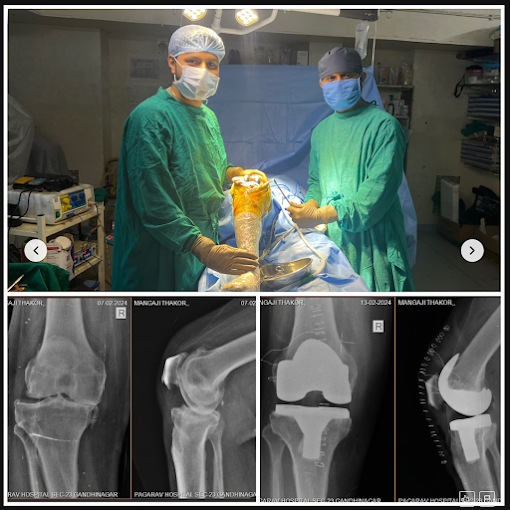

My mother had a successful knee replacement at Ved Orthopedic Hospital. Dr. Dhruv Patel's expertise, compassionate care, and advanced treatment made her recovery smooth. She’s now walking pain-free and confident again. Truly grateful!

DHAMELIYA PIYUSH

My father underwent total knee replacement surgery under the care of Dr. Dhruv Patel, and we couldn't be more satisfied. Dr. Patel is highly knowledgeable, skilled, and exceptionally kind in his approach. His guidance and care throughout the treatment made the entire journey smooth and reassuring. We are truly grateful for his expertise and recommend him to anyone seeking orthopedic care in Gandhinagar.

Punitkumar R Patel Ex. Engr